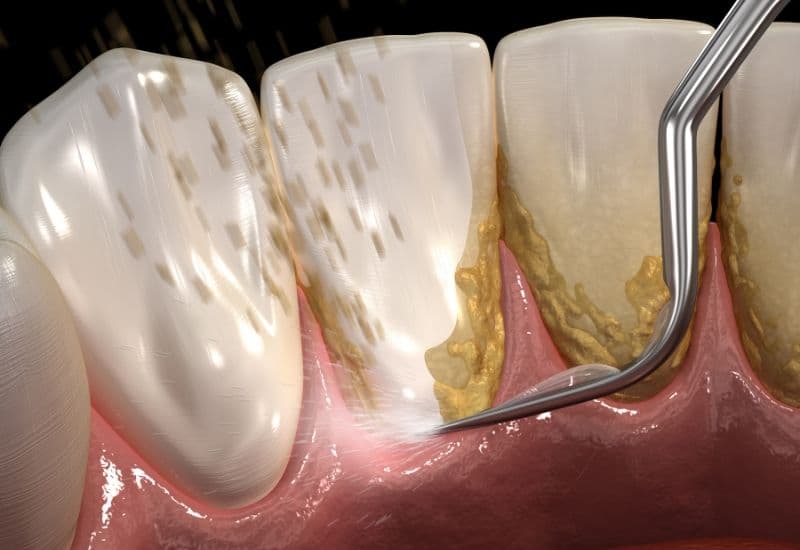

Vôi răng là lớp cứng bám trên bề mặt răng, thường tích tụ dọc đường viền nướu. Cụ thể, dưới đây là các bước chính trong quá trình hình thành vôi răng:

– Khoáng hóa mảng bám: Khi mảng bám tiếp xúc với khoáng chất trong nước bọt, như canxi và phốt phát, quá trình khoáng hóa xảy ra. Trong quá trình này, các khoáng chất trong nước bọt làm mảng bám từ từ cứng lại và trở thành cao răng. Cao răng tiếp tục tích tụ và cứng hóa theo thời gian nếu không được loại bỏ. Càng để lâu, cao răng càng cứng và càng bám chặt vào bề mặt răng, khiến việc loại bỏ càng trở nên khó khăn.

– Lấy cao răng: Nha sĩ sử dụng dụng cụ lấy cao răng phát ra sóng siêu âm giúp phá vỡ cao răng một cách nhẹ nhàng mà không làm hại đến răng. Nha sĩ cũng có thể sử dụng các dụng cụ thủ công để loại bỏ các mảnh cao răng còn lại, đặc biệt là ở những khu vực khó tiếp cận.

Dụng cụ lấy vôi răng phát ra sóng siêu âm được sử dụng để giúp phá vỡ vôi răng một cách nhẹ nhàng.